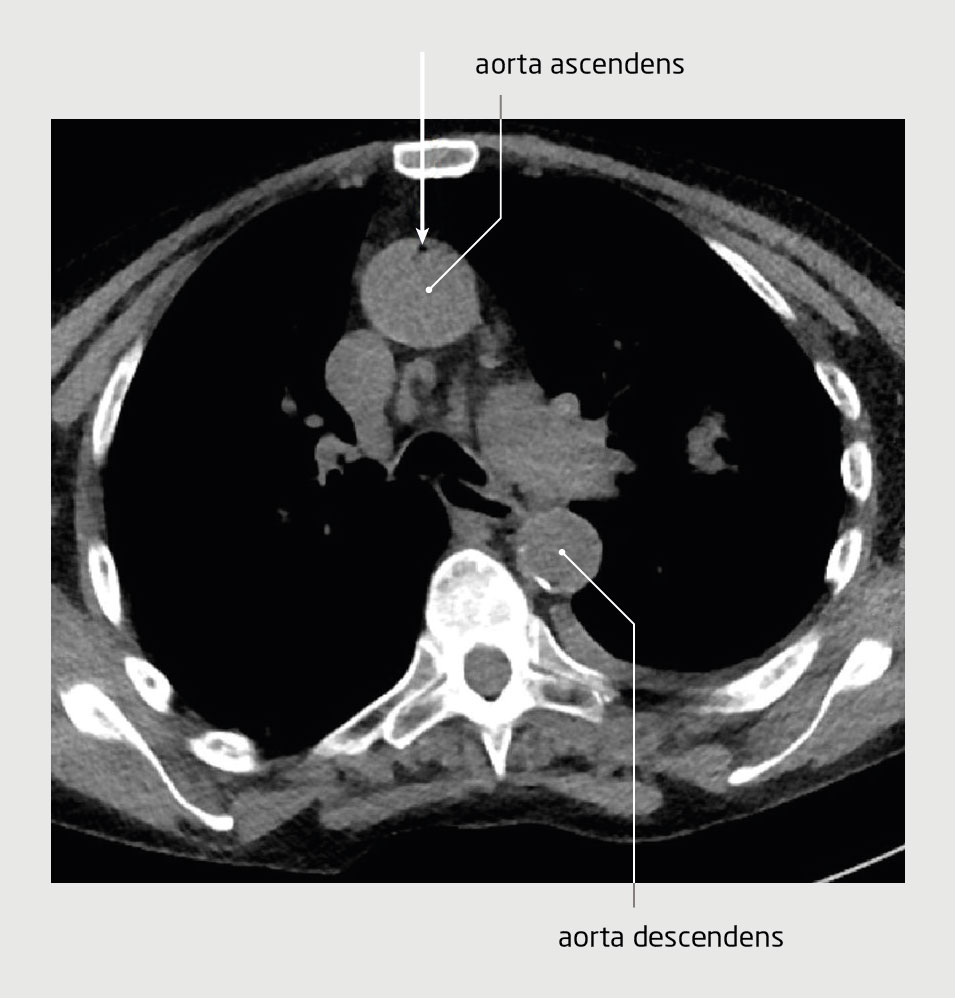

Bij een iatrogene gasembolie is gas aanwezig in de vasculaire structuren, meestal als gevolg van een medische procedure. Zowel arteriële als veneuze gasembolieën kunnen klachten veroorzaken; gasembolieën in de coronairvaten of de cerebrale arteriën kunnen leiden tot een hart- of herseninfarct.

Een 79-jarige vrouw onderging een CT-geleide longbiopsie. Enkele minuten later ontwikkelde ze neurologische klachten. Na toediening van zuurstof verbeterde het klinisch beeld aanvankelijk, maar later verslechterde het opnieuw. Op basis van het klinisch beeld werd de werkdiagnose ‘luchtembolie’ gesteld. De patiënte werd behandeld met hyperbare zuurstoftherapie. Daarna herstelde ze volledig.